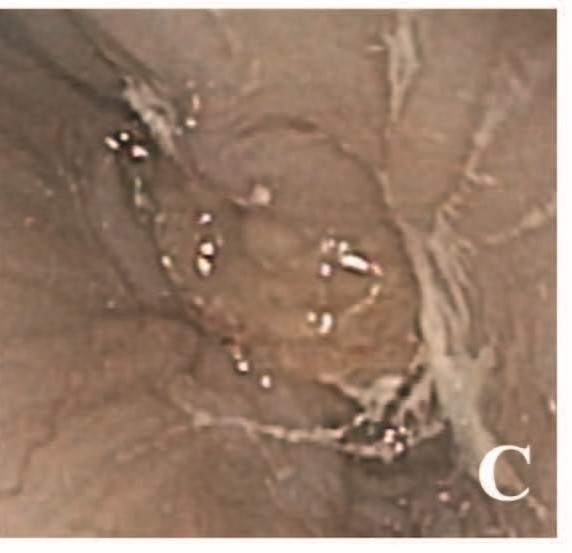

食管内镜见肿块自黏膜突出(图1C),色白、表面无溃疡,完全阻塞管腔,镜身无法进入胃内。活检强烈提示食管鳞状细胞癌。

图1. (C) 食管内镜图像,可见白色肿瘤组织自食管壁突出并完全阻塞管腔。